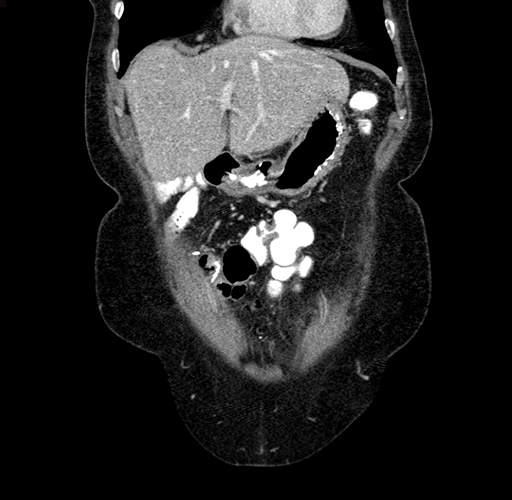

Pre-Chemo: Coronal Venous

Coronal Venous